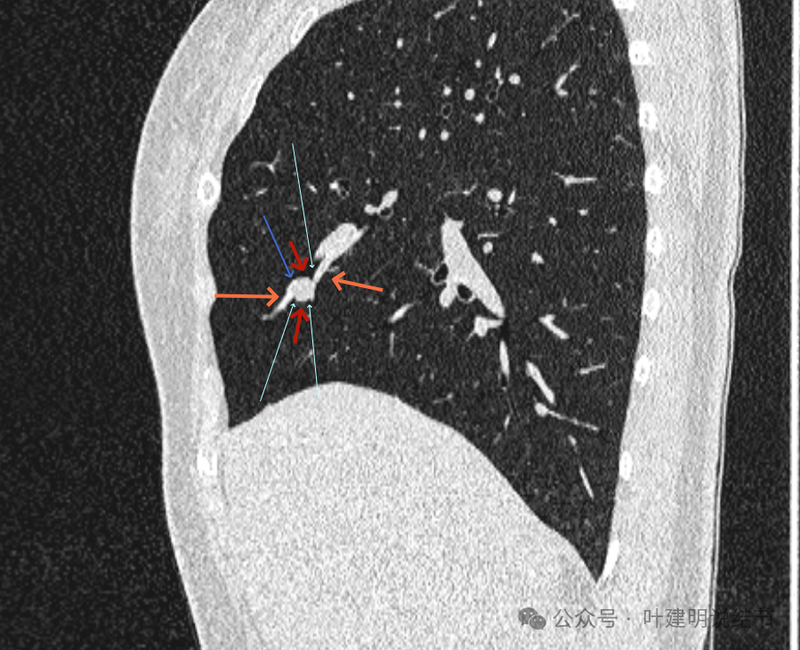

再看冠状位影像:

血管与病灶的关系,两者密度稍不同,天蓝色细箭头所指是分界线。

血管征明显。

血管围着病灶,病灶有膨胀性,表面欠平滑。

不而有膨胀性,血管贴着并被压迫。

边缘欠平滑,邻近血管间隙欠清晰。

血管贴着,结节膨胀。

也示血管与病灶的关系。

结节实性。

纵隔窗这个角度明显见到蓝色箭头所指的血管被病灶侵蚀,而且血管与病灶密度的不同。